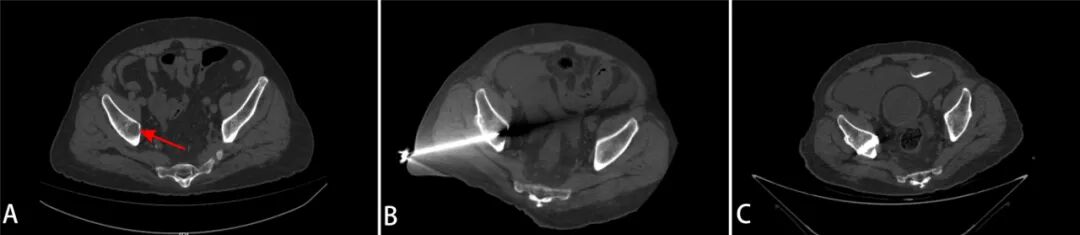

第一步:腫瘤消融。在CT引導(dǎo)下,微創(chuàng)介入科主任胡鴻濤通過一根細(xì)長的消融針,精準(zhǔn)置入病灶中心,利用熱消融技術(shù)滅活“燙死”腫瘤細(xì)胞,從根源上處理局部病變。

第二步:骨水泥成形。消融后,骨與軟組織科馮和林主任利用同一穿刺路徑向被破壞的骨空腔內(nèi)注入醫(yī)用骨水泥。骨水泥迅速凝固后,像混凝土一樣強(qiáng)化骨骼結(jié)構(gòu),恢復(fù)髖臼的承重功能。

術(shù)前髖臼破壞(A),消融針經(jīng)通道置入病灶(B),骨水泥注入骨質(zhì)缺損處(C)

該方案將病灶處理與結(jié)構(gòu)重建相結(jié)合,是當(dāng)前肢體骨轉(zhuǎn)移瘤治療的微創(chuàng)技術(shù)之一。手術(shù)僅通過一個(gè)穿刺點(diǎn)完成,出血量少,患者在清醒狀態(tài)下完成操作,整體過程較為平穩(wěn)。